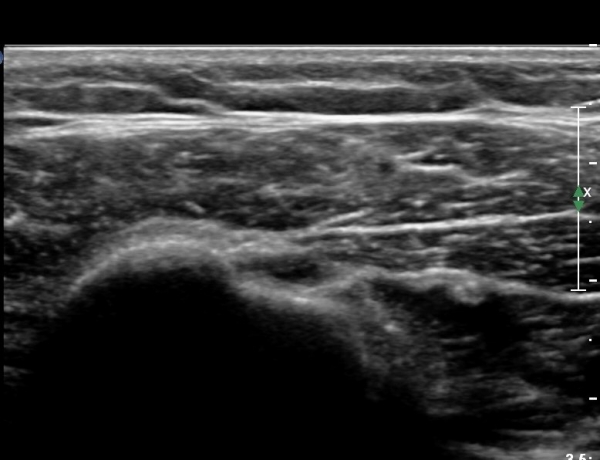

ÃÊÀ½ÆÄ °Ë»ç

´ë°áÀý°ú °ßºÀÇϺο¡ ¹æ»ç¼± Åõ°ú¼º °¨¼Ò(sclerosis)°¡ °üÂûµÈ´Ù(÷ºÎÆÄÀÏ).